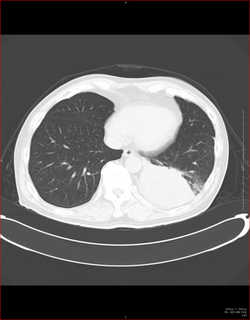

こちらを見て下さい。

わかりにくいかもしれませんが、このあたり。

気管が追いにくい、無くなっているようにも見えます。

CTで見ると…